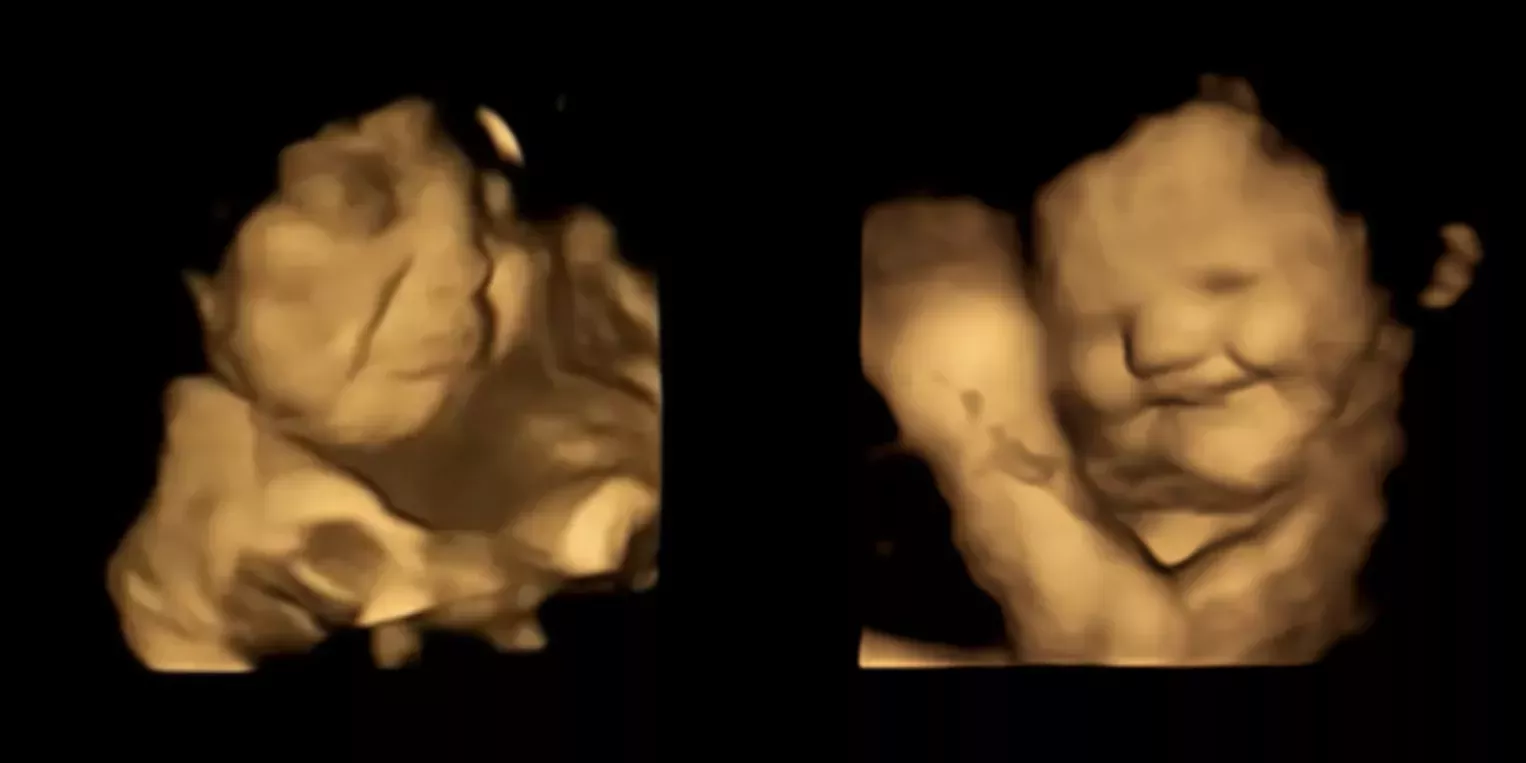

En un estudio realizado con un centenar de mujeres embarazadas del Reino Unido -publicado en línea en la revista Psychological Science-, los investigadores observaron que los fetos sonreían después de que sus madres comieran zanahorias y fruncían el ceño al consumir col rizada. Los fetos tenían entre 32 y 36 semanas de gestación.

Los investigadores utilizaron imágenes de ultrasonidos en 4D para observar las expresiones faciales de los fetos. La tecnología de vanguardia les permitió captar imágenes más precisas, cuadro a cuadro, en comparación con las técnicas de imagen más antiguas.

Unos 20 minutos después de que las mujeres ingirieran las cápsulas, los escáneres mostraron que los fetos expuestos al sabor de zanahoria respondían con más expresiones faciales que sugerían risas o sonrisas, mientras que los expuestos al sabor de col rizada apretaban los labios en una mueca.

Las imágenes de la ecografía mostraban movimientos faciales similares a los de los niños o adultos que prueban algo amargo, como levantar el labio superior o fruncir el ceño con el labio inferior. Sin embargo, eso no significa que los fetos expresaran un disgusto temprano por la col rizada.